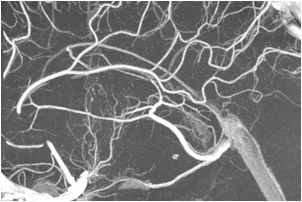

1.「新型FPD搭載 AlluraClarity FD20/15」- 大幅な被ばく低減と高画質を両立したClarity IQテクノロジーと新型16bitFPD(フラッ トパネルディテクタ)による高精細な画像

脳血管内治療におけるイメージガイダンスの究極の目的は、明瞭にデバイスが視認でき効率の良いナビゲーションを可能にすること。世界中のクリニカル パートナーと共に築き上げた“ライブイメージガイダンス”技術とともに、強力に脳血管内治療をサポートする。

コーンビームCTテクノロジーの最新アプリケーションであるVasoCT*1による3Dイメージングも、「NeuroSuite」を構成する重要なアイテムである。16bitのFPDによる頭蓋内の穿通枝レベルの微細な血管や周辺解剖および最新デバイスの描出*4は、脳血管内治療のイメージガイダンスとして強力なサポートツールとなる。